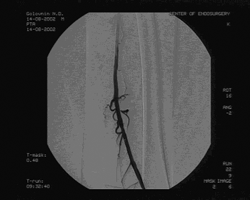

Пациенту произведена баллонная ангиопластика и стентирование правой ОПА и ОБА, реканализация обеих ПБА с последующей баллонной ангиопластикой и стентированием через подколенные пункционные доступы с обеих сторон. Баллонная ангиопластика ОПА и ОБА проводилась баллонами диаметром 10 и 7мм с последующим стентированием, диаметр и длина стентов 10 мм и 60 мм в ОПА, 8 мм и 40 мм в ОБА, соответственно. Реканализация ПБА проведена с обеих сторон гидрофильным проводником "Road Runner" с последующей баллонной ангиопластикой баллонами диаметром 6 и 7 мм и стентированием. Во всех артериях установлены ZA-стенты соответствующего диаметра и длиной от 40 до 80 мм. Всего установлено 6 стентов: в правую ОПА, правую ОБА, правую ПБА, 3 стента в левую ПБА: 1 в проксимальной части, начиная от устья , 2 в зоне Гунтерова канала. (см. рис. 3)

Рис. 3. Контрольная ангиография после реканализации и стентирования левой ПБА.